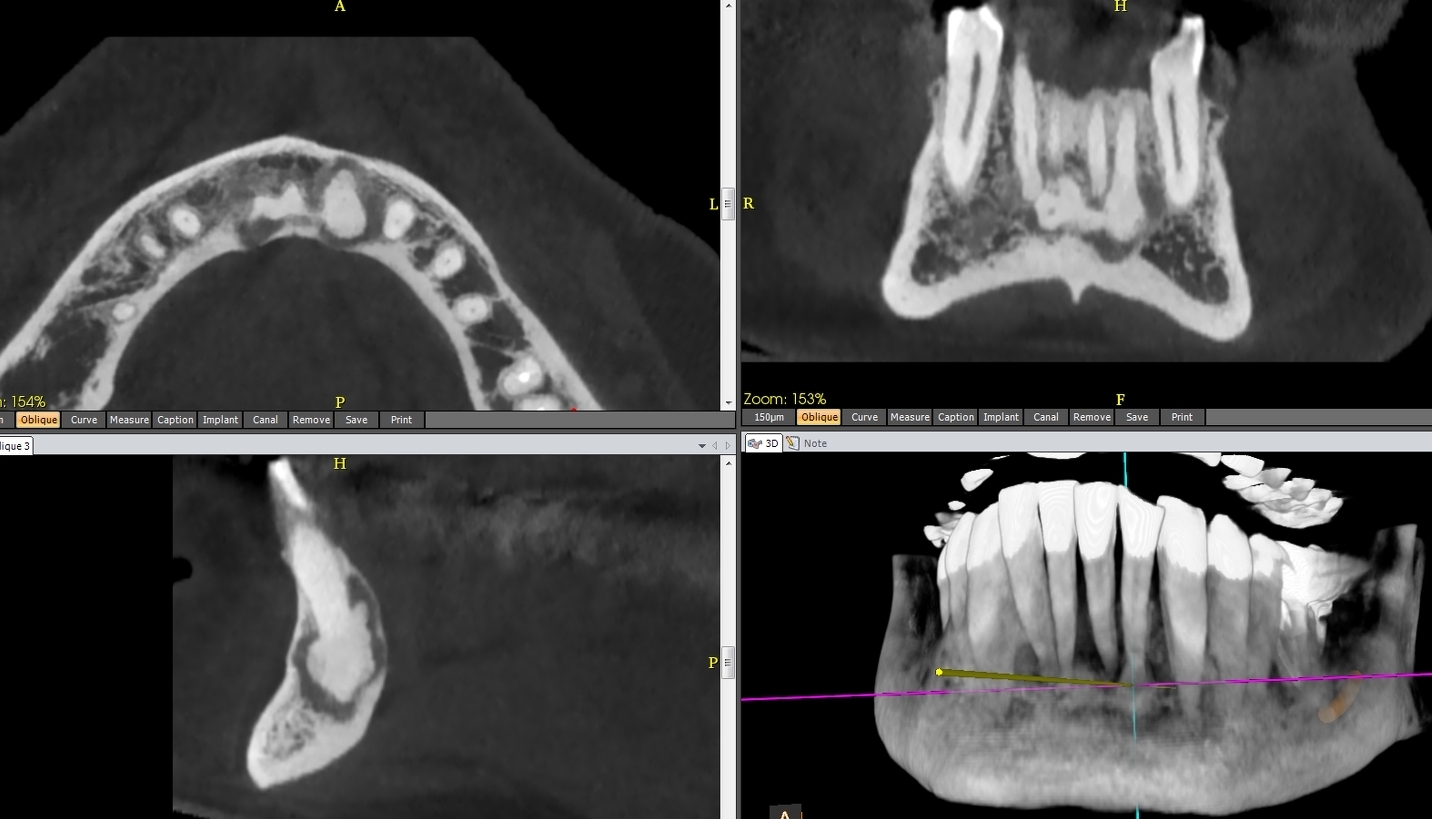

A. Les dysplasies osseuses (ou cémento-osseuses) focale et périapicale, (Fig.1 à 3), (anciennement cémentome) sont les plus fréquentes lésions fibro-osseuses périapicales non néoplasiques ; proches du fibrome cémento-ossifiant, beaucoup plus rare et dont on a parfois du mal à la distinguer. De découverte le plus souvent radiologique, chez une femme d’âge moyen, le plus souvent à la mandibule :

– antérieure (affectant volontiers les apex incisifs ou canins) pour la dysplasie osseuse périapicale,

– ou postérieure pour la dysplasie osseuse focale,

– elles évoluent toujours sur dent vivante, en trois stades :

> stade I : dit « ostéolytique », lacune apicale, correspondant à du tissu fibreux, sur dent saine (Fig.1) ;

> stade II : intermédiaire, un dépôt de cément se formant au sein de la clarté apicale (Fig.2) ;

> stade III : hyperdensité apicale cernée par liseré clair périphérique (Fig.3)

2. FIBROME OSSIFIANT ou. CEMENTO-OSSIFIANT (Fig.6)

Tumeur bénigne fibro-osseuse assez rare, le fibrome ossifiant touche l’adulte jeune et est siège de mandibulaire postérieur dans 80% des cas.

Cliniquement muette, elle peut entraîner déplacements dentaires et déformations osseuses.

Elle est radiologiquement variable, allant de la forme lacunaire pure soufflant les corticales sans les rompre, avec parfois des calcifications, des travées ou des îlots denses, à la formation multiloculaire hétérogène, mixte ou radio-opaque, mais à limites nettes. Le diagnostic différentiel est parfois difficile avec la dysplasie fibreuse ou la dysplasie osseuse.